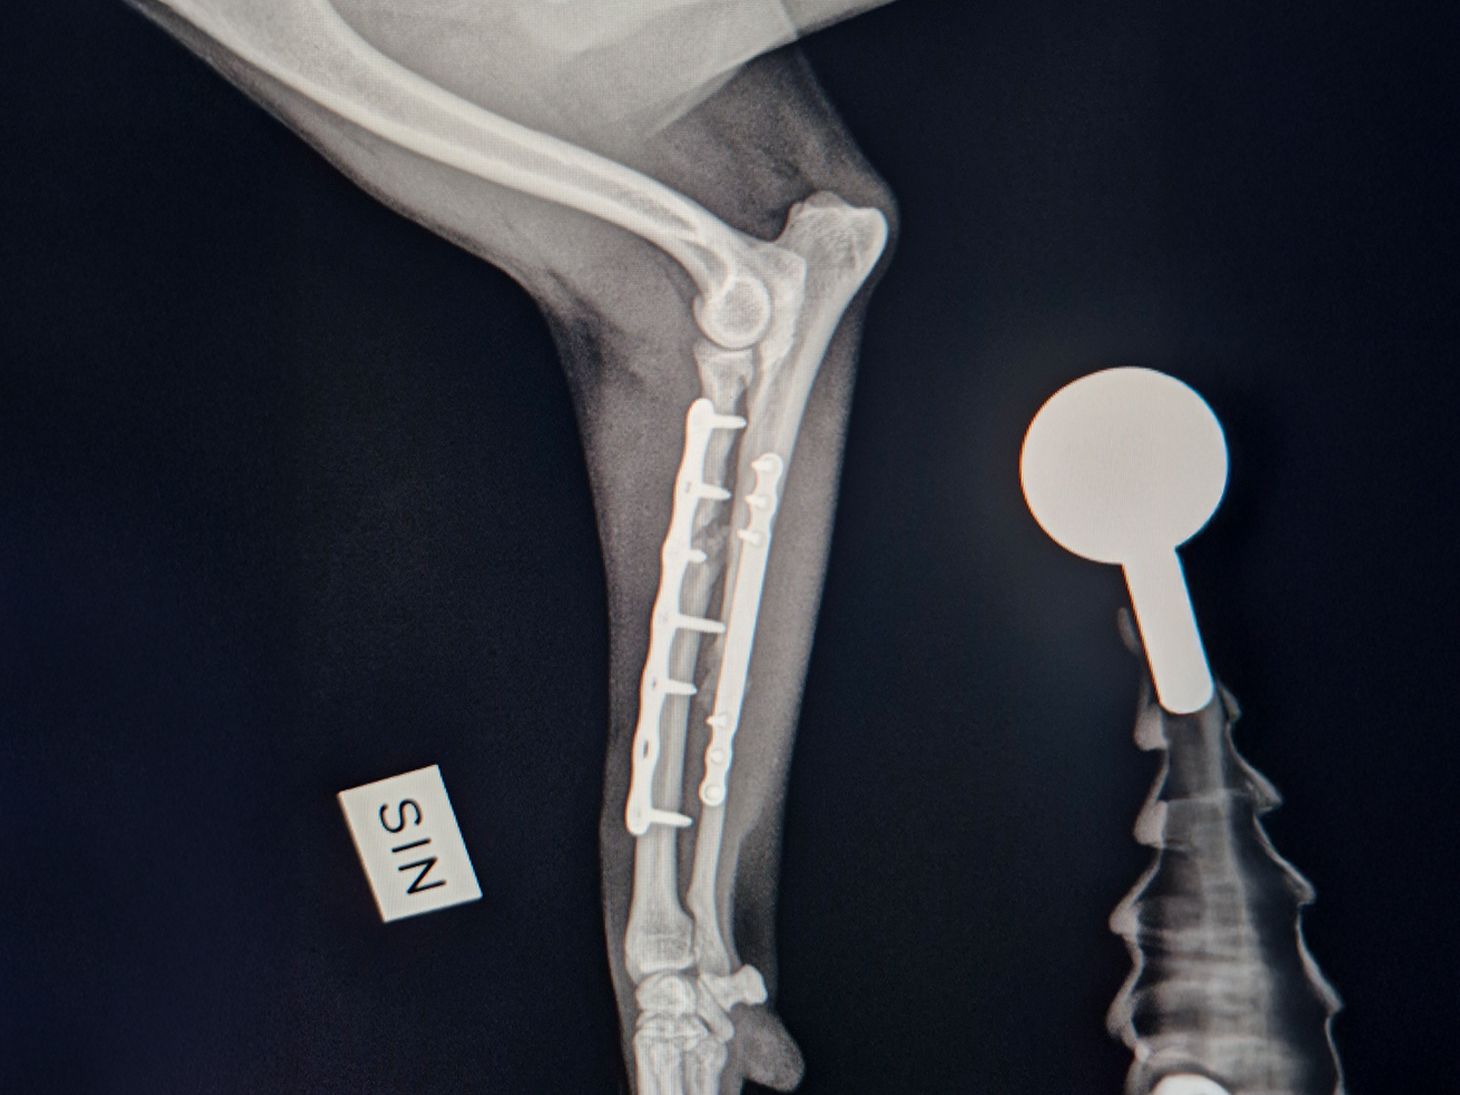

- The severely comminuted radius fracture was stabilized using a 2.0 mm titanium LeiLOX plate, specifically chosen to manage the comminution in combination with a supportive repair of the ulna.

- The ulna fracture was addressed with our innovative 1.0 mm titanium LeiLOX plate, secured by 1.3 mm locking screws. This combination provided robust, yet minimally disruptive, fixation crucial for a small patient. The surgical site was thoroughly flushed, and the patient received Cefazolin both perioperatively and for three days post-op to manage the open wound.

- X-Ray Confirmation: The surgery sites were fully healed, with no discomfort upon palpation. X-rays showed advanced healing with significant callus formation and all implants intact.

This case is a powerful example of how the entire LeiLOX system, including the new 1.0 mm plate, provides the secure, tissue-friendly stability needed for complex fractures. It allows for highly specific and robust stabilization in small animal orthopedics, enabling a rapid and complete return to function, even in highly active patients. It is inspiring to see this technology fully restore the beloved family member's mobility and quality of life!